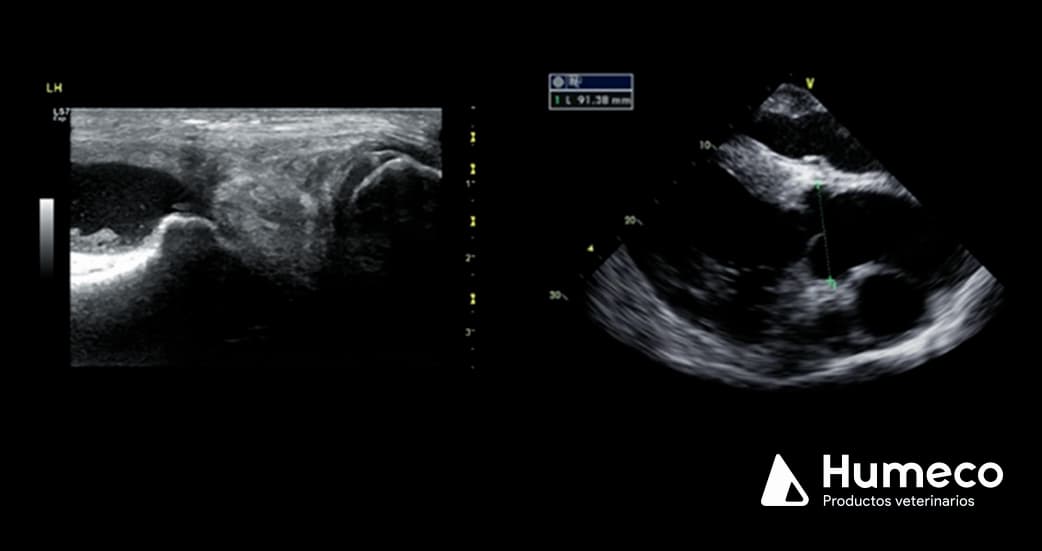

- Tendones y ligamentos de la extremidad distal, por ejemplo, lesiones centrales de SDFT.

- Articulaciones, por ejemplo, lesión meniscal en la rodilla.

- Evaluación de la anatomía y función cardíaca, por ejemplo, investigación de soplos.

- Para fines oftalmológicos y musculoesqueléticos de las extremidades distales se requiere una sonda lineal de alta frecuencia.

- Cardíaco, una sonda de matriz en fase (sector) de baja frecuencia.